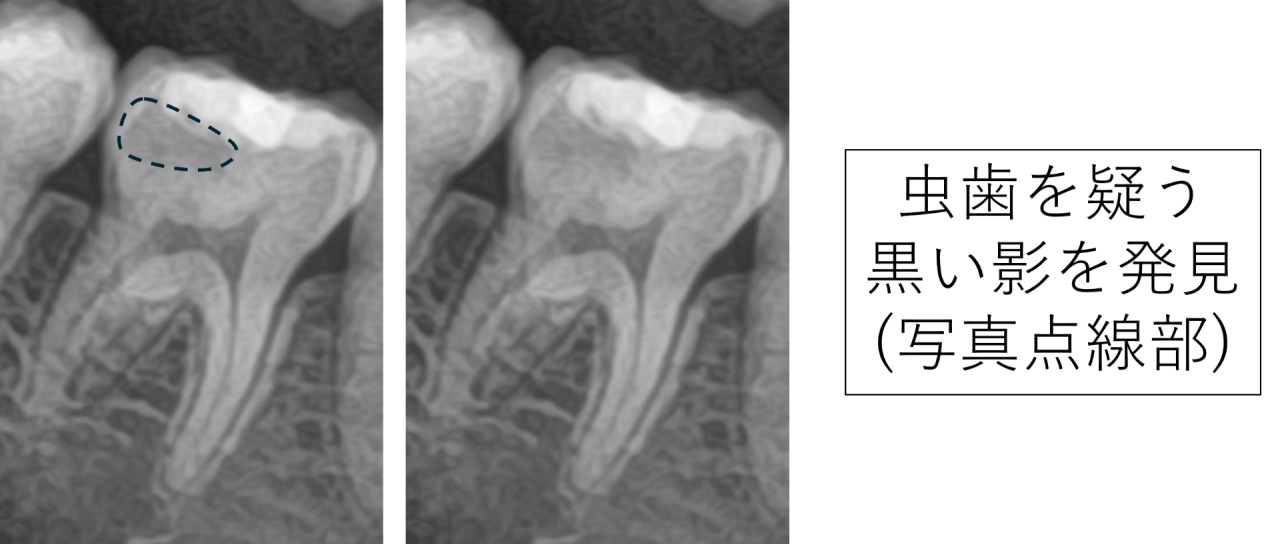

レントゲンを撮影した所、右下の奥歯に虫歯を疑う大きな黒い影がありました。

患者様に説明した所、その歯は半年前くらいに治療したそうです。確かにプラスチックのつめ物(レジンといいます)がされているため、治療はされています。黒い影は虫歯以外に、セメントも黒い影として見えることがあるので、どちらかははっきりしません。そこでCTを撮影しました。

CTを見ると、黒い影がとても大きいことがわかりました。白く写るプラスチックのつめ物と比べてもとても大きいため、おそらくセメントではなく虫歯の取り残しだろうと診断しました。